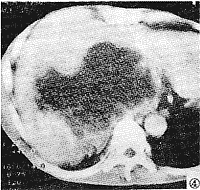

参照手术所见,将肿块分为囊实混合性,囊性和实质性三类:①囊性:CT平扫为均匀低密度灶,囊内无增强,包膜及分隔可轻至中度强化(CT值升高10~40 Hu),此类肿瘤共7例,3例为囊性淋巴管瘤,CT值<16 Hu,3例为成熟型囊性畸胎瘤,CT值>20 Hu(图1),另一例为巨大分化良好型平滑肌肉瘤,其内可见多个房隔强化,囊内CT值26~42 Hu(图2)。②囊实混合性:特点为大囊性病灶加一部分实质,囊性部分CT值较高,15~27 Hu,实质部分20~42 Hu(图3),此类共计2例,均为间叶组织恶性肿瘤。③实质性:共计22例,又可分为不均匀和均匀性。不均匀实性,标本切面上见肿块内有多发灶性液化,坏死或小囊变及多发出血。此类最多见,计21例,CT表现为不均匀性团块,密度不均,见片状不规则低密度灶,增强后见不均匀性强化(图4及图6),此类肿瘤良、恶性均较多见,其中脂肪肉瘤5例,平滑肌肉瘤6例,神经源性肿瘤3例及分类不明者2例,血管内皮肉瘤1例。均匀实质性肿瘤1例,为平滑肌瘤。此外,在血管内皮肉瘤及神经节细胞瘤、畸胎瘤中可见散在斑点状,结节状钙化。

图1 腹膜后成熟型囊性畸胎瘤。CT示左肾上极内侧3.5 cm×2.5 cm的占位性病变,密度均匀,CT值+24 HU,边缘光整,有包膜,囊内容无增强

图4 肝右叶后方见一巨大实质性肿块,境界欠清晰,密度不均,中心见大片不规则坏死区,肝右叶受压,CT误诊为肝癌,病理为血管内皮肉瘤

CT具有较高的密度及空间分辨力,较客观地显示肿块位置,大小及毗邻关系,还可借助增强扫描进一步了解病变内部及周围情况,本组腹膜后肿瘤CT检出率达100 %,定位正确率达94 %,较小的肿瘤CT定位较易,肿瘤大时定位常较困难[1,2],由于CT固有横断扫描方式,尤其是相邻器官受压萎缩时,脂肪间隔不易显示,易将原发腹膜后肿瘤误诊为肝、胰或肾上腺肿瘤,本组中,由于肿块较小,有1例腹膜后成熟型囊性畸胎瘤误诊为肾上腺肿瘤(图1),1例腹膜后血管内皮肉瘤误诊为肝癌(图4),但由于螺旋CT的出现,可通过多平面重建克服这一缺陷。